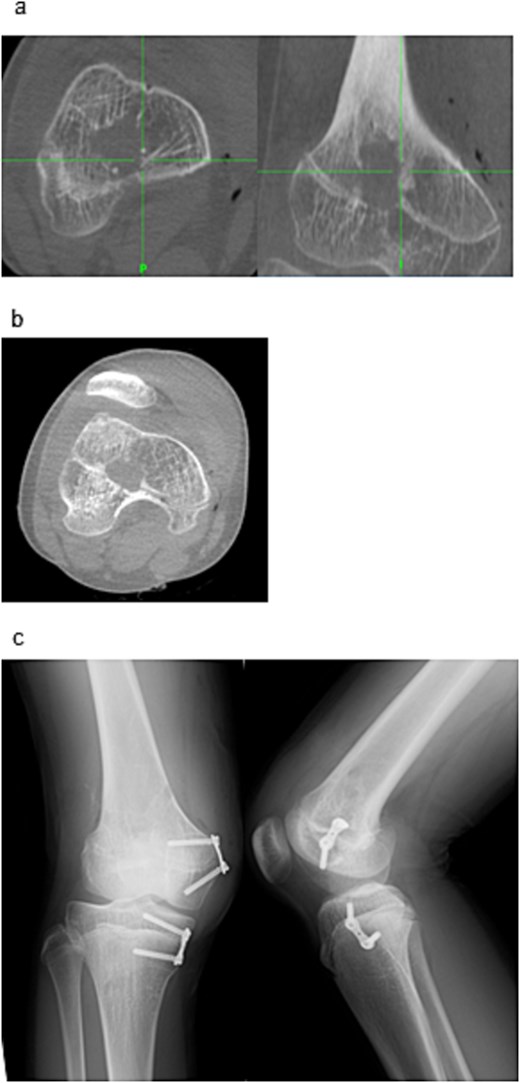

Examination revealed full range of motion in the affected knee (0–140°) and no pain during walking. Spinal malleolar distance assessment showed a leg length discrepancy of 30 mm (shorter right limb). Radiography showed valgus alignment with a femorotibial angle (FTA) of 162° on the right leg and 172° on the left (Fig. 1a–c). CT revealed early epiphyseal closure of the distal femur, indicating physeal bar formation near the posterior cortical bone (Fig. 1d–f). Accordingly, physeal bar resection was planned.

Preoperative radiographic and CT findings. (a) Anteroposterior radiograph of the right knee. (b) Lateral radiograph of the right knee. (c) Full-length standing anteroposterior radiograph of the lower extremities showing valgus deformity (femorotibial angle: right, 165°; left, 172°). (d) Coronal CT image. (e) Sagittal CT image. (f) Axial CT image showing early epiphyseal closure of the distal femur caused by a physeal bar (arrow), located adjacent to the posterior cortical bone.